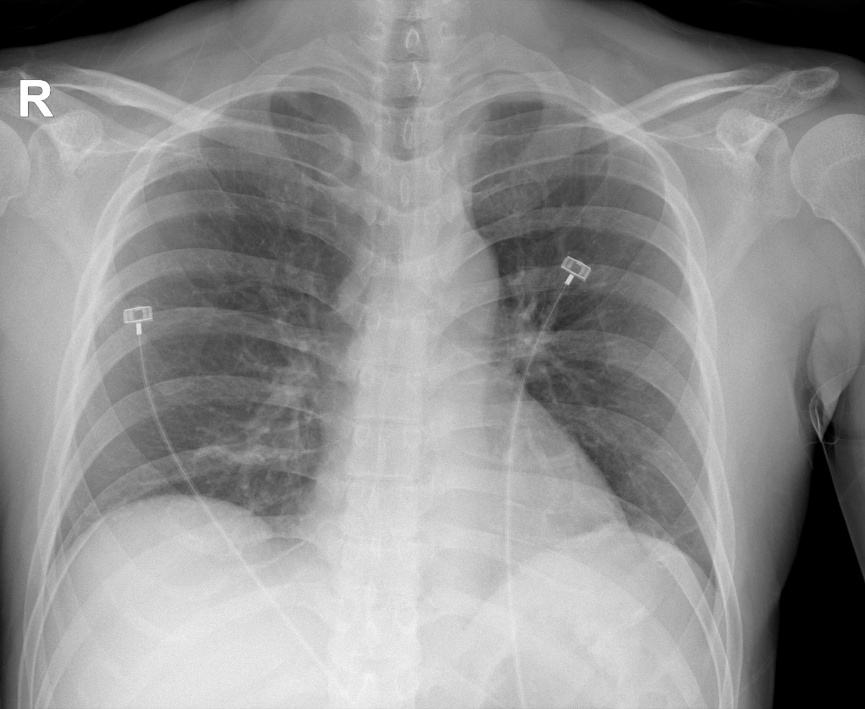

이후 환자 혈압 121/78 mmHg, 심박수 88회/분으로 안정 상태 유지되고, 흉부 방사 선상 천공 의심 소견 없어,[그림3] 위산억제제 포함한 약제 처방받아 귀가하였습니다.

[그림3] 단순흉부방사선 소견